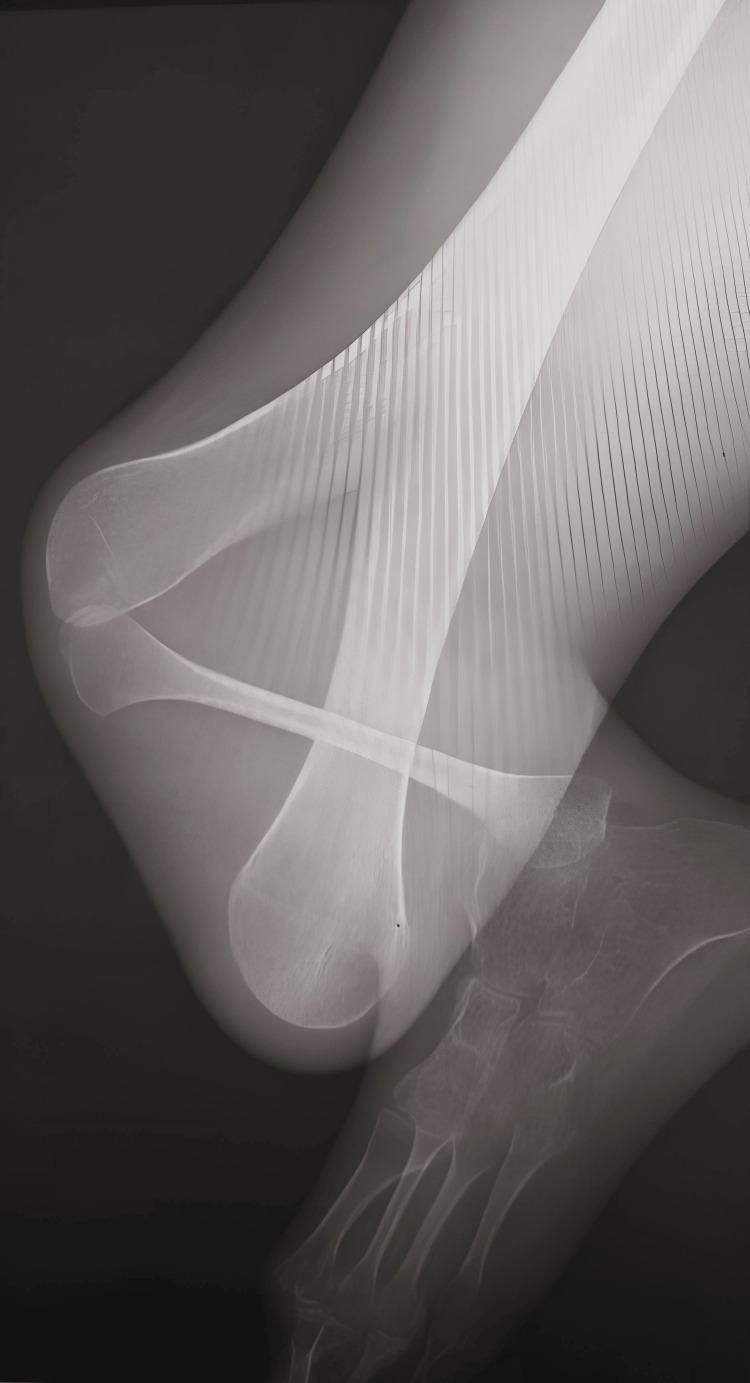

Gollop-Wolfgang Complex (GWC) is a rare congenital musculoskeletal anomaly marked by distal femoral duplication and tibial aplasia. While often linked with other systemic defects like those in the VACTERL association, our case uniquely presents an isolated manifestation of this complex. The exact genetic cause of GWC isn't fully understood, highlighting a gap in our knowledge of limb development disorders. Treatment typically involves early surgical intervention, such as knee disarticulation and prosthetic fitting, though limb salvage procedures are also recognized. Despite its global rarity (fewer than 200 reported cases), GWC is rarely documented in Africa. This report details a case of GWC from North Africa, offering insights into its presentation and management within this demographic. We present a 14-year-old Moroccan male, the third of three siblings, who presented with a right lower limb deformity evident since birth. Clinically, he showed a characteristic Y-shaped distal thigh due to palpable femoral bifurcation, a fixed knee flexion deformity, and apparent absence of the tibia. Radiographs confirmed a bifurcated right distal femur and right tibial hemimelia (Jones Type Ia). Notably, our patient had no associated upper limb, cardiac, neurological, or renal deformities, nor ectrodactyly or absent radii, distinguishing his presentation from many reported cases. Prenatal diagnosis wasn't established due to a lack of antenatal ultrasound follow-up. Despite thorough counseling on surgical options, including amputation for prosthetic fitting, the patient declined intervention due to fears of postoperative pain and complications. Consequently, we initiated a conservative management plan focused on rehabilitation, crutch use, unipodal balance exercises, and gait training to optimize his functional independence. This case report underscores the diagnostic challenges of GWC and highlights the critical role of patient autonomy in treatment decisions, particularly when conventional surgical approaches are met with patient refusal. Our experience suggests that a dedicated, non-surgical rehabilitation pathway can be a viable alternative, even in complex skeletal anomalies. This unique case contributes valuable clinical data, expanding the limited global understanding of GWC and emphasizing the need for comprehensive documentation of rare conditions to refine personalized management strategies.